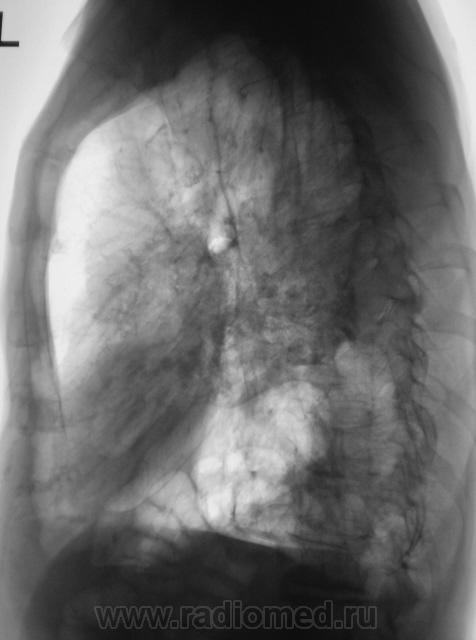

Томограммы.

Какие мнения?